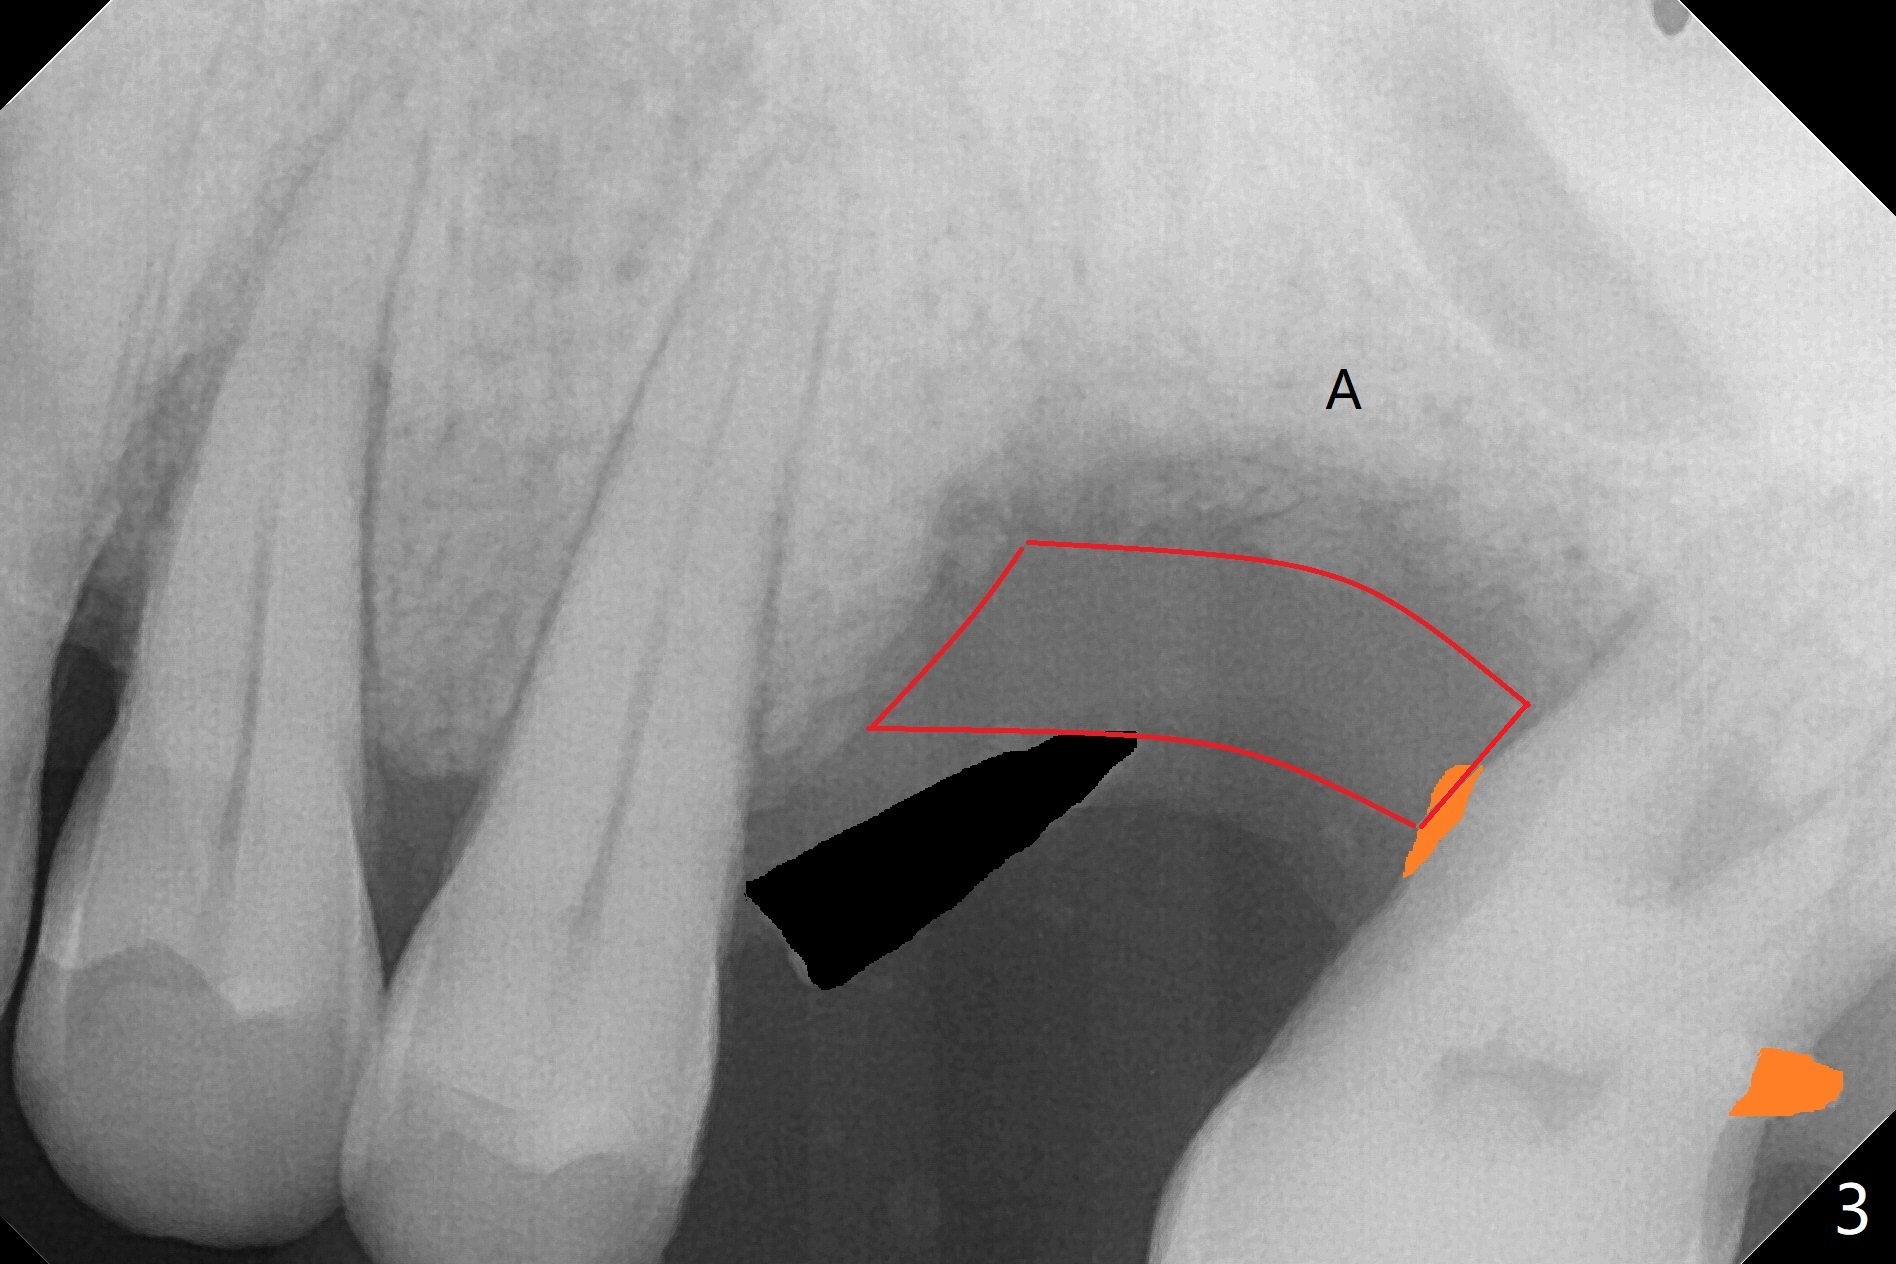

50岁男两年前不肯拔牙左上6(图一),现在要求及早拔除植骨(图二),几个月后与左下7一起植牙。我们准备深洗(图三橘黄色)后拔除残根(黑色),翻瓣后植入粘性骨块(红色)。为了解释手术步骤,给牙槽骨(A)做冠状切面,如图四黑色四方形,B:颊侧;P:腭侧;而粉红色代表牙龈(G)。图五红线表示切口,弯箭头:翻瓣,如图六。然后植入粘性骨块(图七:S)。盖上PRF膜(图八蓝线)以及不可吸收膜(图八绿线),最后使用PTFE缝线(图九:黑线)稍微关闭伤口,不至于压扁骨块。这样可行吗?需要使用tenting screw防止骨块塌陷?为了避免使用后者,索性直接植入植体(图十:绿色)和基台(浅蓝色),周围堆放骨粉(红色)。覆盖PRF膜(图十一:深蓝色),缝合(细线)。骨密度1200-1400单位;骨粘膜厚度4.2毫米,血供好(图十二;图十三:G: 牙龈)。翻瓣(图十四:箭头),植入植体(绿色),放置基台(粉红色)和骨粉(红色)。由于基台占据空间,缝合应该是松弛的,下面骨粉不易移位,在暴露螺纹附近愈合。Jennifer: flap surgery; since osteotomy will be created in a slope with most likely distal deviation, design the long axis of the implant mesial by 1 mm occlusally.